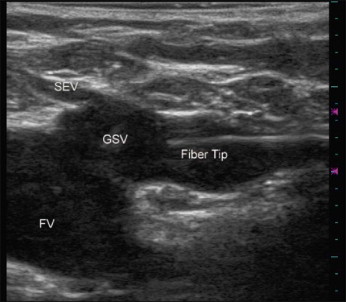

Set the laser to continuous mode and select the power to be used. Re-verify placement of the laser tip with ultrasound ( Fig. 9.4 ).

Figure 9.4

Longitudinal (sagital) ultrasound image of the saphenofenoral junction demonstrating a 400 micron laser fiber tip in the great saphenous vein (GSV) just below the superficial epigastric vein (SEV). FV, femoral vein